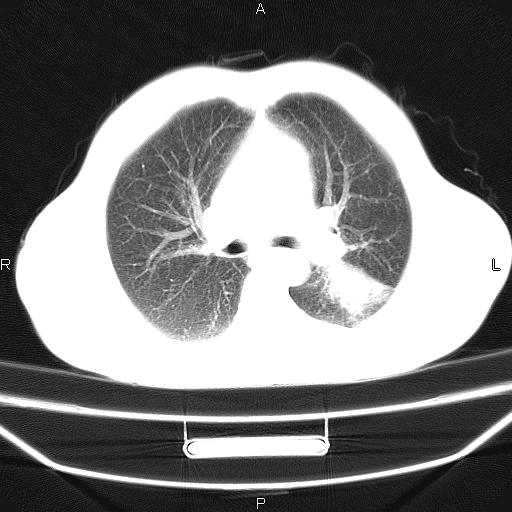

患者,男,40岁。间断发热,咳嗽二十余日。体温最高达38.9° 在当地诊所抗炎治疗三天后体温降至正常,患者自行停药。今又发热。胸片示,左下肺阴影。

左下肺片状高密度影,境界模糊,密度不均,考虑感染性病变可能性大,建议抗炎治疗后复查。左肺门增大,不除外占位性病变,必要时支气管镜检。